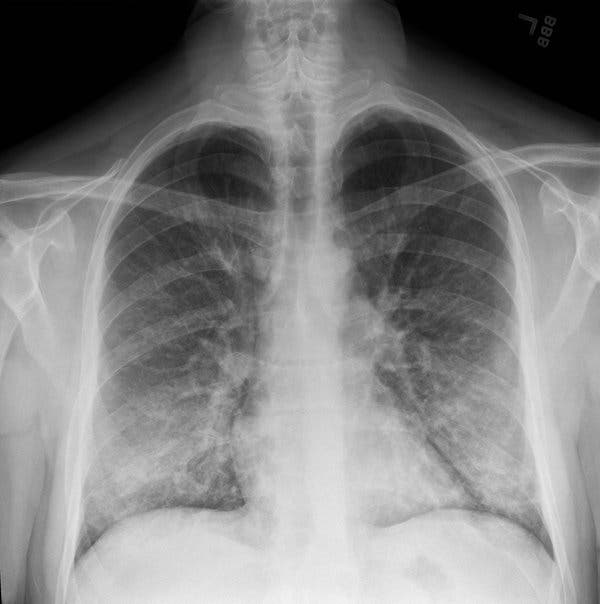

A second person has passed away from a mysterious lung illness linked to vaping, according to health officials.

Dr. Ann Thomas, the lead investigator on the case and a public health physician at OHA’s Public Health Division, said that the person was ‘otherwise healthy and quickly became very ill.’ Before the patient’s death, a ventilator was required, according to the New York Times.

The patient’s symptoms before death were in line with those of more than 200 reported cases of lung illnesses nationwide linked to vaping currently being investigated by the Centers for Disease Control.

After the first person’s death, the CDC announced their investigation into more than 200 reported cases of severe respiratory illness linked to vaping.